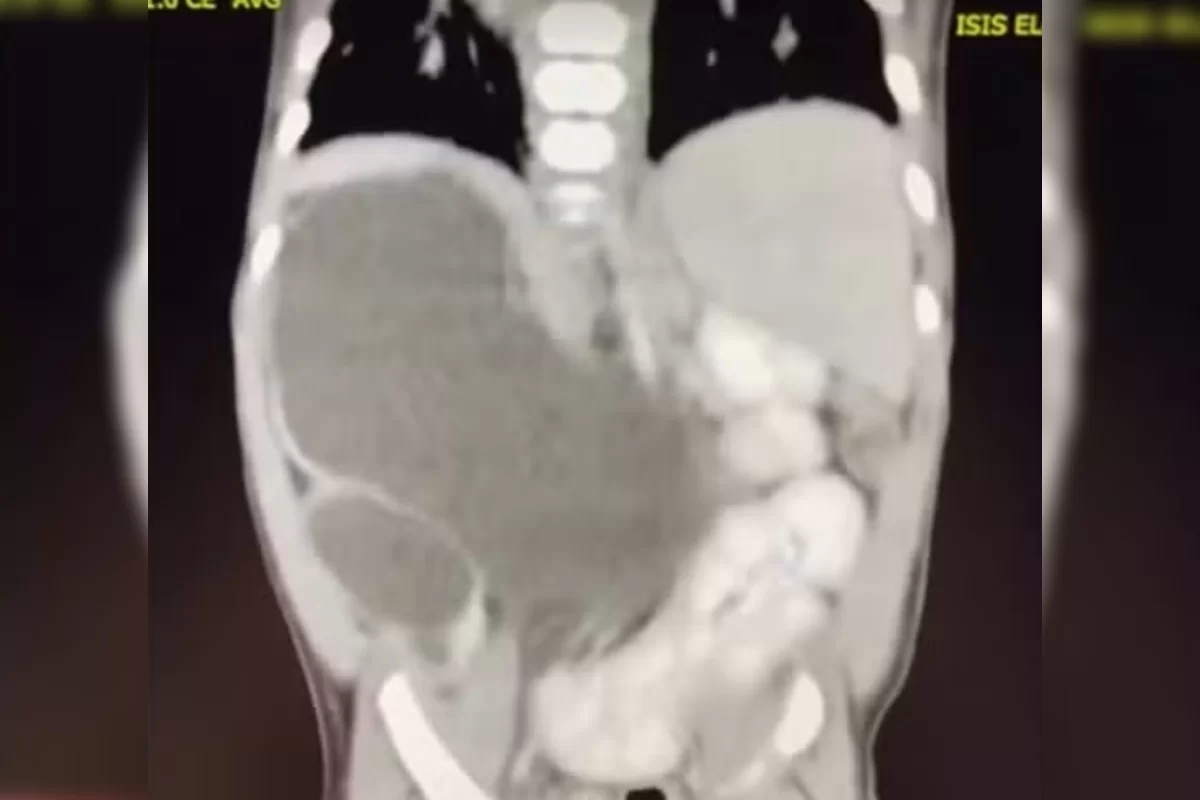

Incluída nos casos raríssimos da medicina, uma menina nasceu com quatro rins. Hoje com 1 ano e 1 mês, a pequena Isis Eloah Ferreira Alves está entre os cerca de 100 casos da medicina documentados na literatura mundial. O caso, publicado pelo G1, é é conhecido na medicina como “rins supranumerários” e demanda acompanhamento.

Aos 5 meses, quando houve a necessidade de Isis passar por uma cirurgia, os médicos confirmaram que ela tinha nascido com quatro rins. Como Formosa fica a cerca de 80 quilômetros do Distrito Federal, a menina hoje é tratada no Hospital da Criança de Brasília (HCB).

Os médicos da unidade explicam que a quantidade superior de rins se dá devido a uma má formação ainda na getação. Ainda não existe explicação porque se desenvolve mais de um rim em cada lado.

O médico que a acompanha, Hélio Buson, afirmou ao G1 que ter vários rins não apresenta anormalidade para o corpo. Assim, os órgãos podem passar despercebidos ao longo da vida e só serem notados na vida adulta. É necessário que haja acompanhamento.